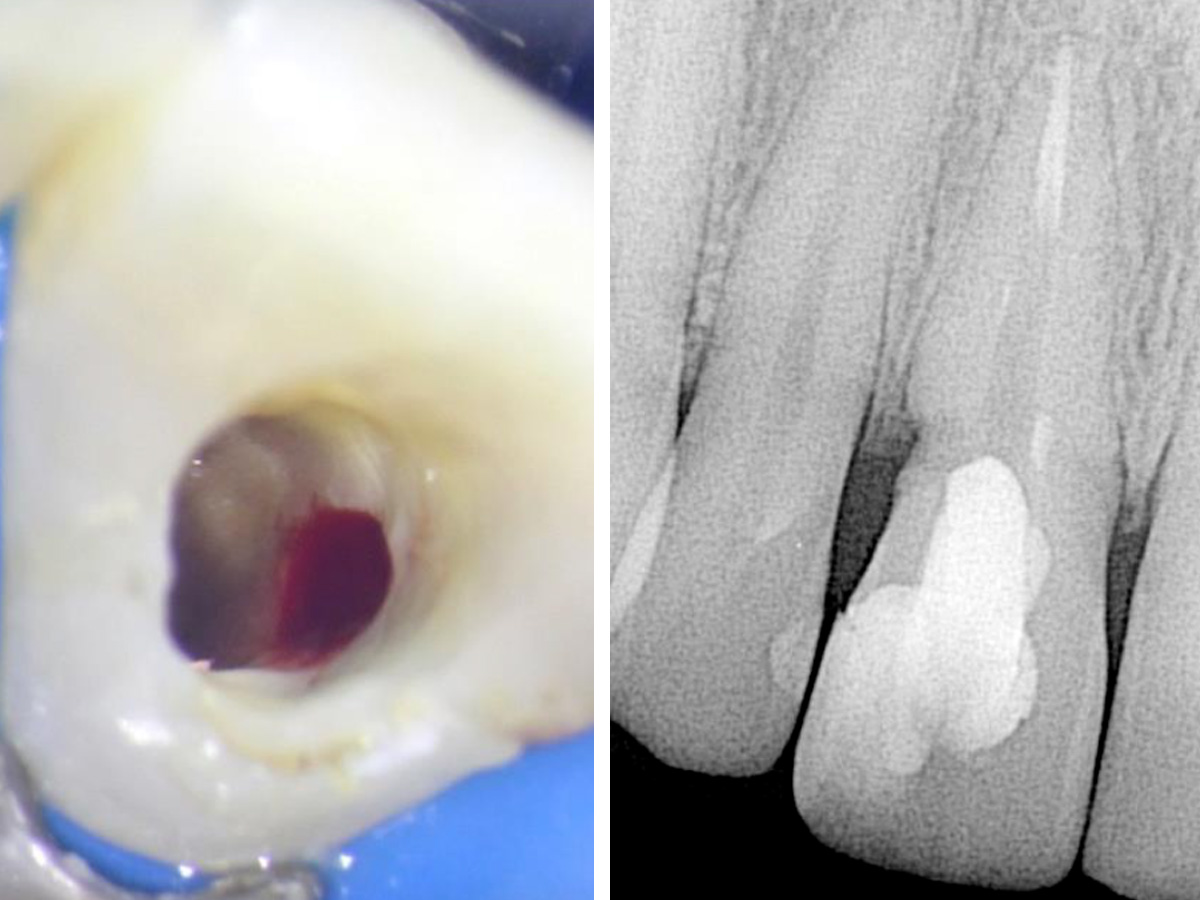

Abbildung 2

Zu sehen ist der blutende Defekt im zervikalen Bereich zu Beginn der Wiedereröffnung des Wurzelkanals.

Zu Beginn der Behandlung wurde zunächst so viel vom Gutta-Percha wie nur möglich entfernt und der Wurzelkanal anschließend desinfiziert. Man konnte eine Blutung des resorptiven Defekts erkennen. Der Kanal und der Defekt wurden mit Kalziumhydroxid gefüllt und der Zugang mit IRM versiegelt (Abb. 2).